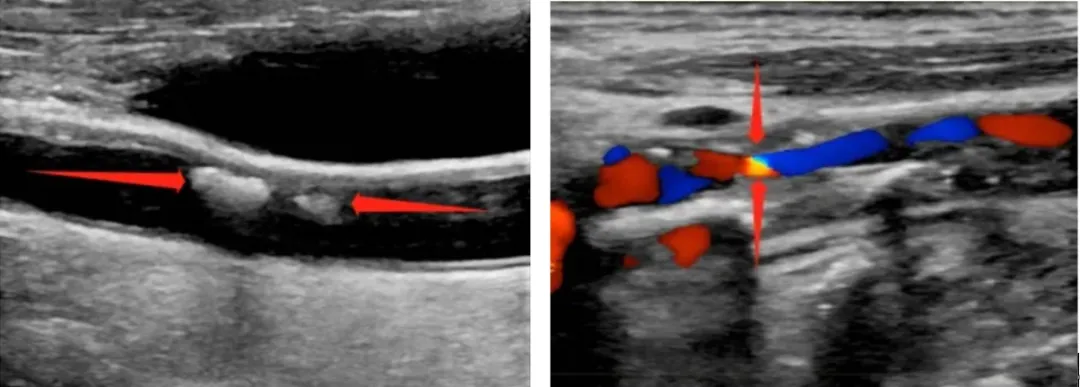

颈动脉超声检查是评估颈动脉疾病的基本检查方法之一,简便、无创、重复性好。颈动脉超声不仅能清晰显示血管内中膜是否增厚、有无斑块形成、斑块的部位、大小、是否有管腔狭窄、闭塞等情况,并能进行准确的测量及定位,还能对检测动脉的血流动力学检查结果进行分析,通过颈动脉超声检查,医生能精准判断患者病情,预估卒中风险,采取相应的预防和治疗措施,提高患者的生活质量,从而降低心血管疾病的发病率。